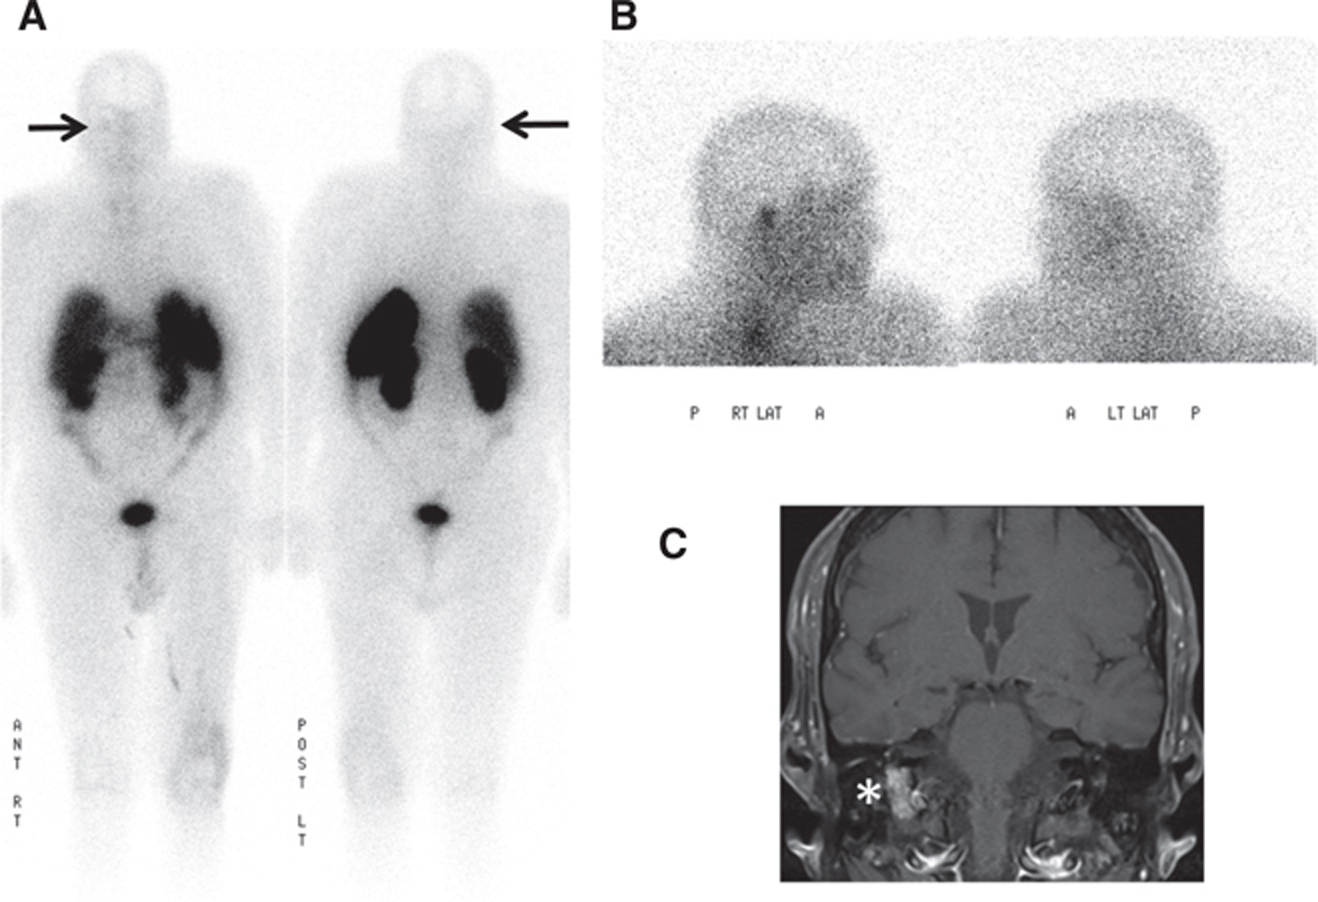

Fig 7

Figure 7 A 65-year-old male patient with right middle ear cavity mass. (A) In-111 pentetreotide whole body planar and (B) lateral spot images of the head performed 24 h after administration of radiotracer show moderate focal tracer uptake in the region of the right middle ear. (C) T1-weighted fat-suppressed post-contrast coronal brain MRI shows an avidly enhancing mass in the right jugular foramen concerning for a glomus tumor. Surgical pathology showed a 1.2 cm × 0.6 cm × 0.3 cm lesion with positivity for synaptophysin and chromogranin on immunohistochemistry, compatible with a paraganglioma.